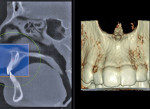

Finally, whether clinicians purchase or simply use the data from CBCT machines in their practice, it is important—perhaps imperative—that they obtain training beyond the manufacturer’s hands-on, in-office introduction. Until trained, a dentist or dental specialist is simply not used to seeing a patient image in the axial plane of section. These types of images, as well as the images in the coronal and sagittal planes and the anatomic data within them, must be mastered before a clinician can feel comfortable using CBCT (Figure 1, Figure 2, and Figure 3).